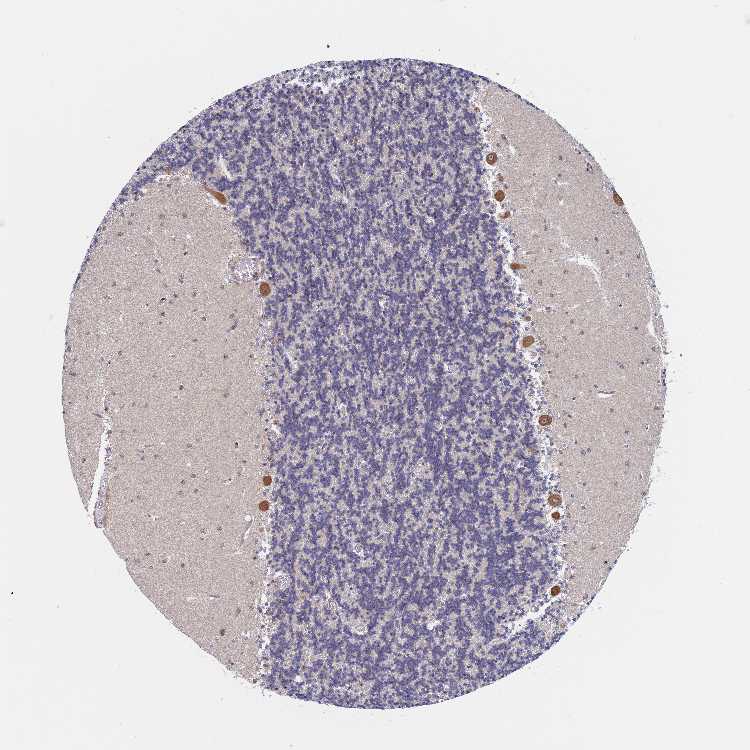

CEREBELLUM - Antibody stainingi

Antibody staining in the annotated cell types in the current human tissue is reported as not detected, low, medium, or high, based on conventional immunohistochemistry profiling in selected tissues. This score is based on the combination of the staining intensity and fraction of stained cells.

Each image is clickable and will lead to virtual microscopy that enables deeper exploration of all samples and also displays staining intensity scores, fraction scores and subcellular localization as well as patient and tissue information for each sample.

Antibody HPA030711Antibody CAB006269

Purkinje cells HighHigh

Cells in granular layer Not detectedMedium

Cells in molecular layer Not detectedHigh